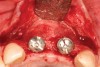

Figure 2  The orientation of the healing abutments after the patient had undergone extraction, guided bone regeneration, and implant placement. Note the wide spacing between the central incisor implants.

Figure 2

Figure 10  Temporary healing abutments are placed immediately following extraction of teeth 8 and 9. Note that there is no damage to the surrounding periodontium due to atraumatic extractions.

Figure 10